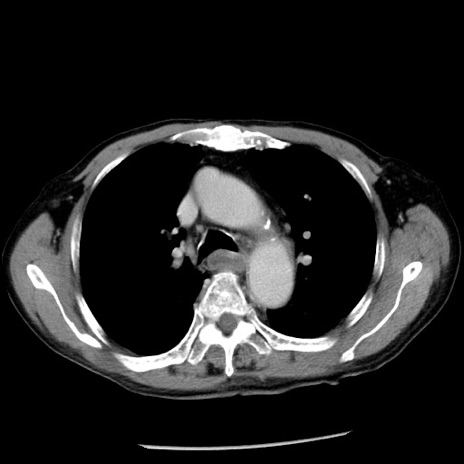

症例26(横断像)

【症例】80歳代男性

【主訴】嘔吐

【現病歴】昨晩2回嘔吐あり、今朝になっても嘔吐あり。来院。

【既往歴】胃潰瘍

【身体所見】意識清明、BT 37.6℃、BP 166/95mmHg、HR 100bpm、SpO2 97%、腹部:平坦・軟、腸蠕動音聴取良好、圧痛なし。

【データ】WBC 21900、CRP 1.46